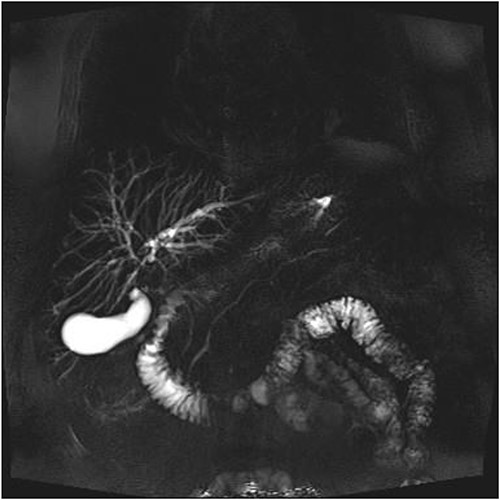

A man in his 70s presented to the emergency department with painless obstructive jaundice with dark urine and pale stools. The patient denied having any fever, nausea, vomiting, or weight loss. Liver function test progressively worsened during the admission peaking at a bilirubin of 287 umol/L (normal 2–20), alkaline phosphatase 694 U/L (normal 30–110), and alanine aminotransferase 160 U/L (normal < 40). Initial assessment on computed tomography and ultrasound raised concerns for primary pancreatic head neoplasm or cholangiocarcinoma (Fig. 1). He subsequently underwent magnetic resonance cholangiopancreatography (MRCP), which showed involvement of the entire common bile duct with no definite stricture or dilatation and no discrete pancreatic head mass (Fig. 2). Positron emission tomography showed abnormal uptake in the intrahepatic and extrahepatic bile ducts, focal uptake in the tail of the pancreas, and lymph nodes in the porta hepatis, retroperitoneum, and right iliac fossa (Fig. 3). Tumour markers revealed a carbohydrate antigen 19-9 (CA19-9) of 3286 kU/L (normal < 34).